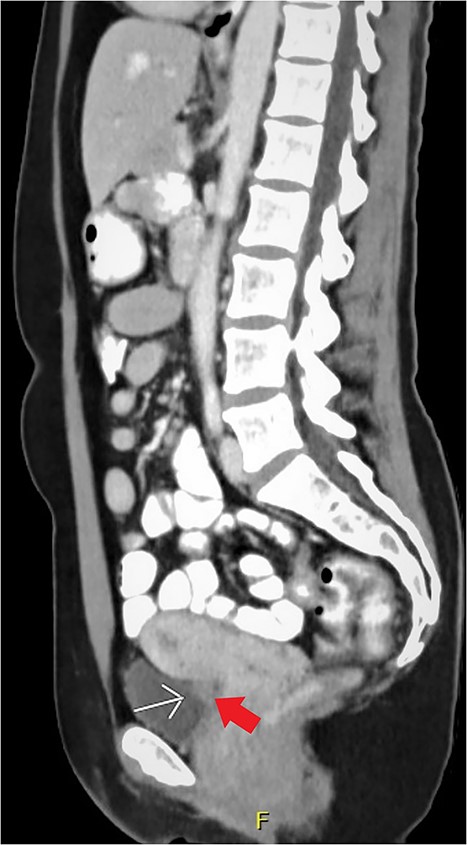

Expert transvaginal ultrasound scan was performed after referral with a CT scan to our tertiary center (Fig. 1). A 1.5–2 cm intramural endometriosis nodule was seen in the posterior bladder wall, not reaching the bladder mucosa (Fig. 2). On ultrasound scan, there was also evidence of adenomyosis of the uterus.

CT scan, sagittal view of the endometriosis nodule in the posterior bladder wall.